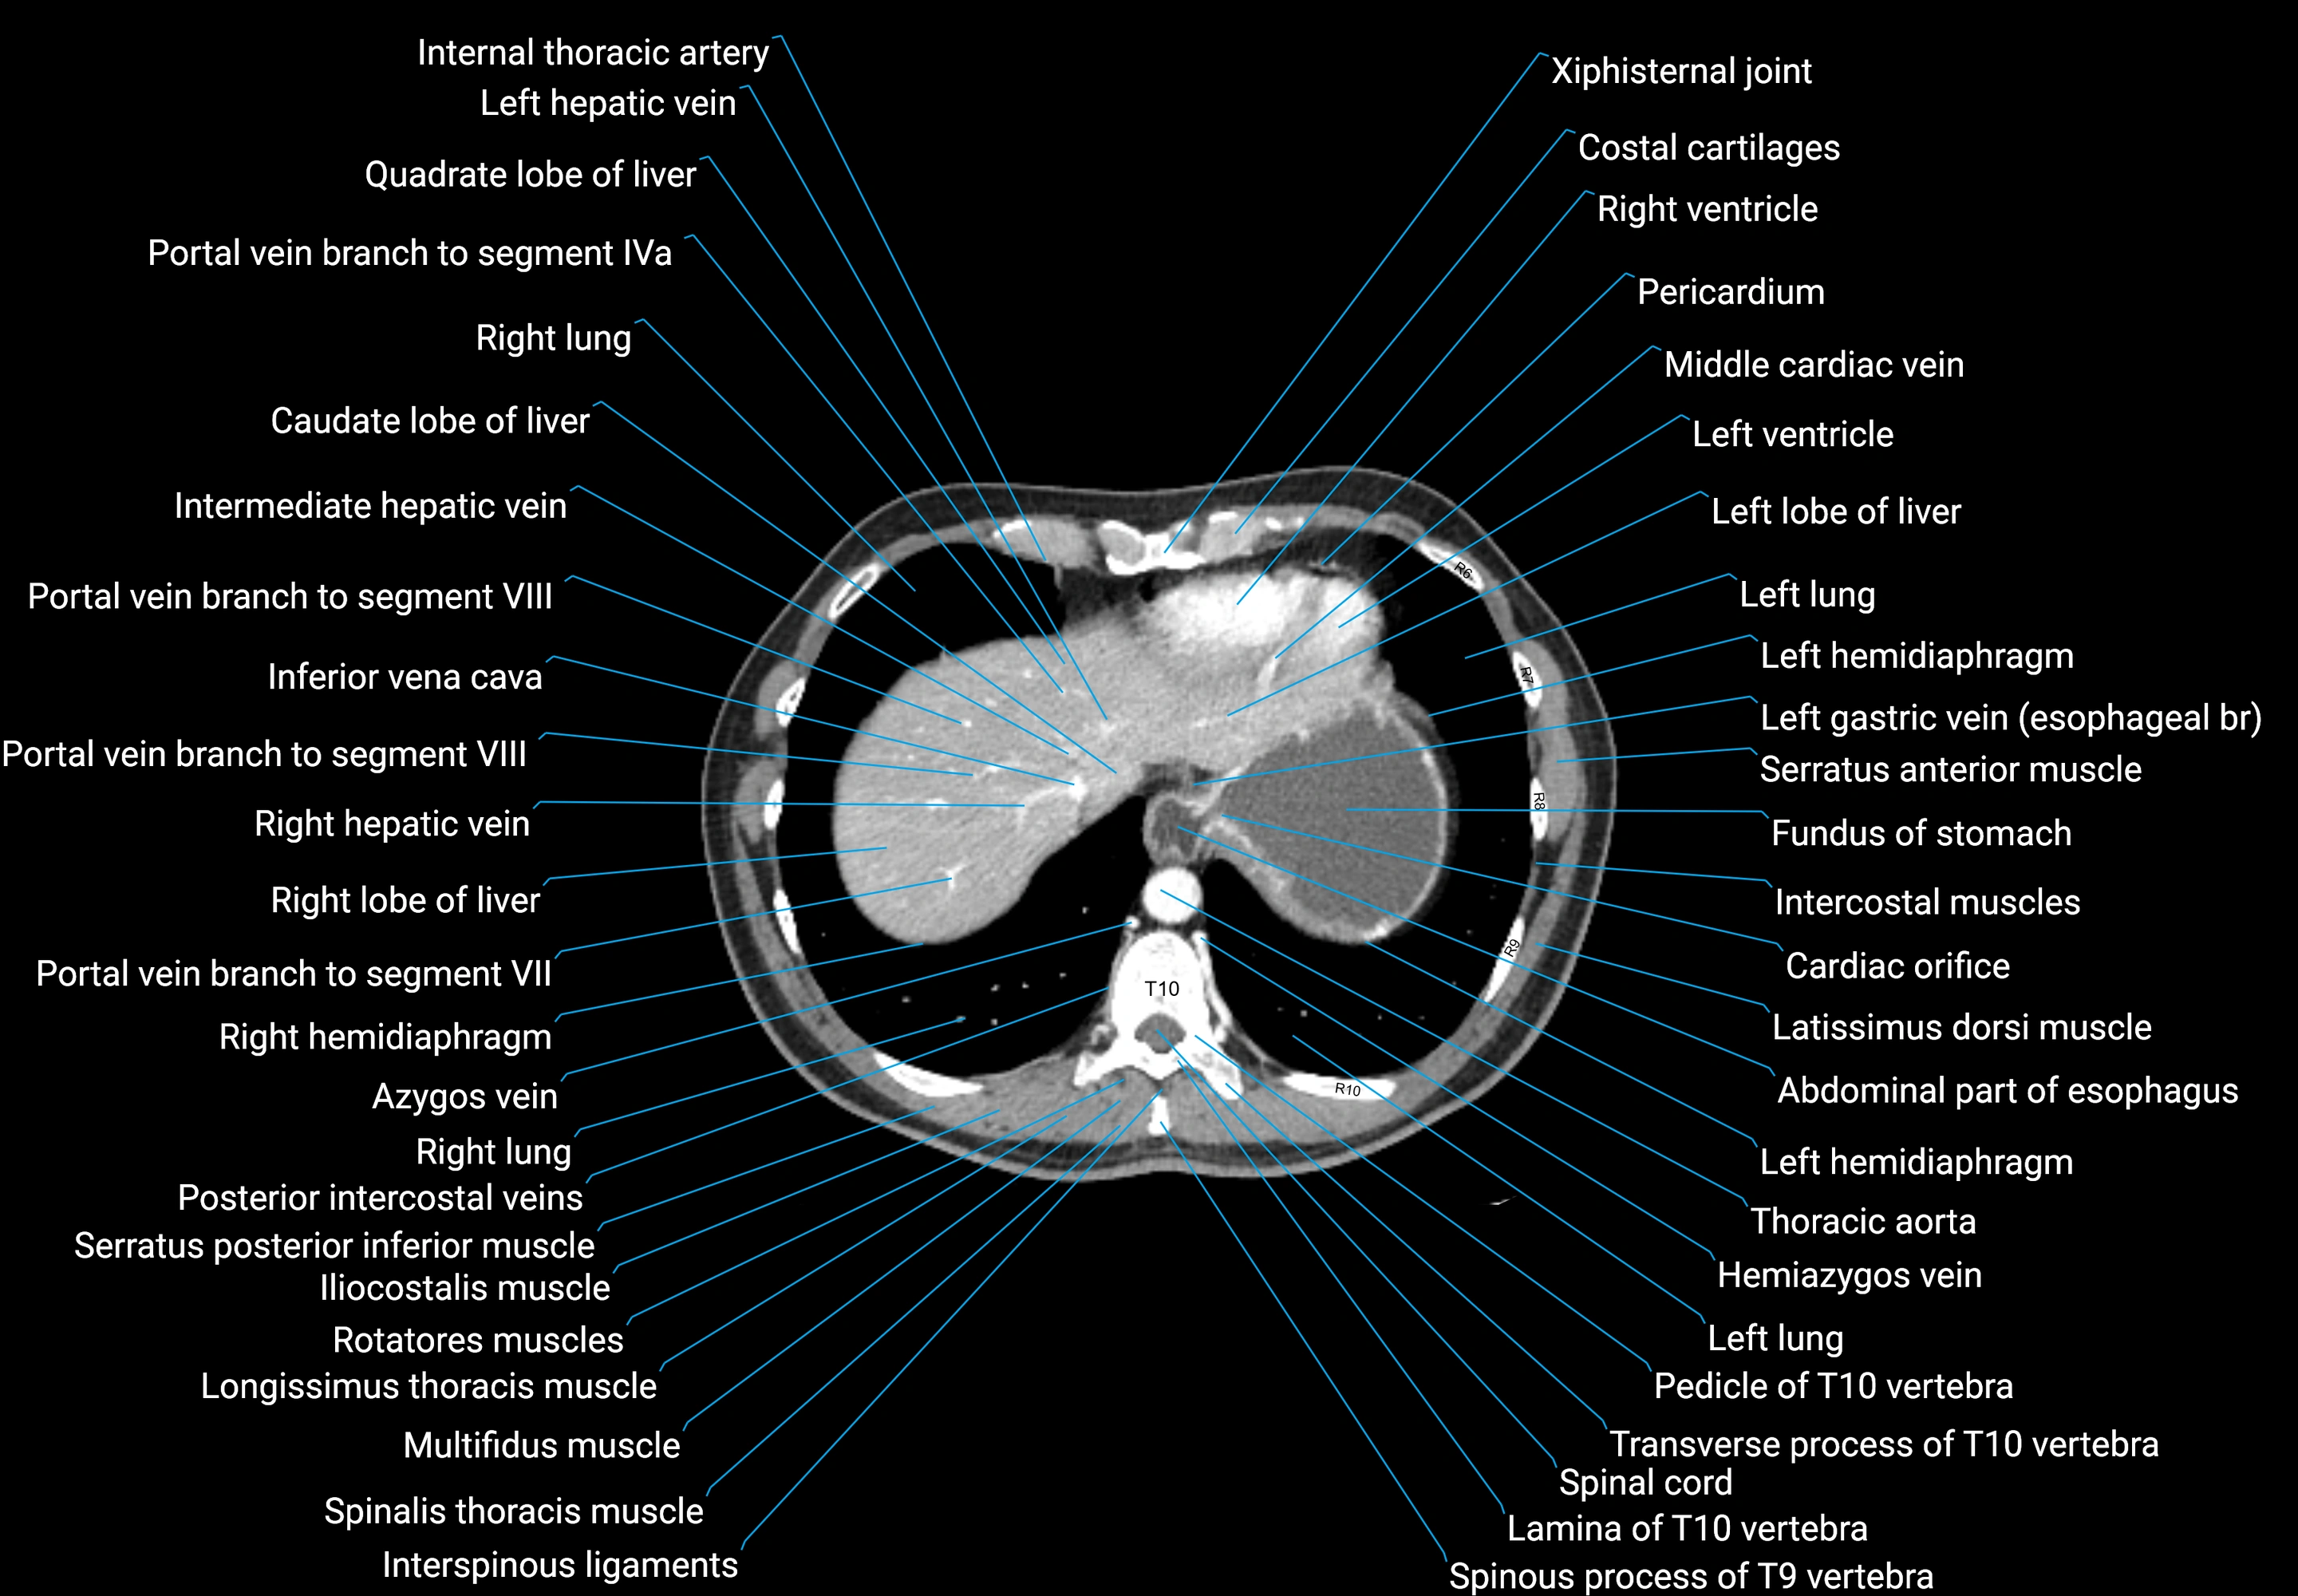

CT images